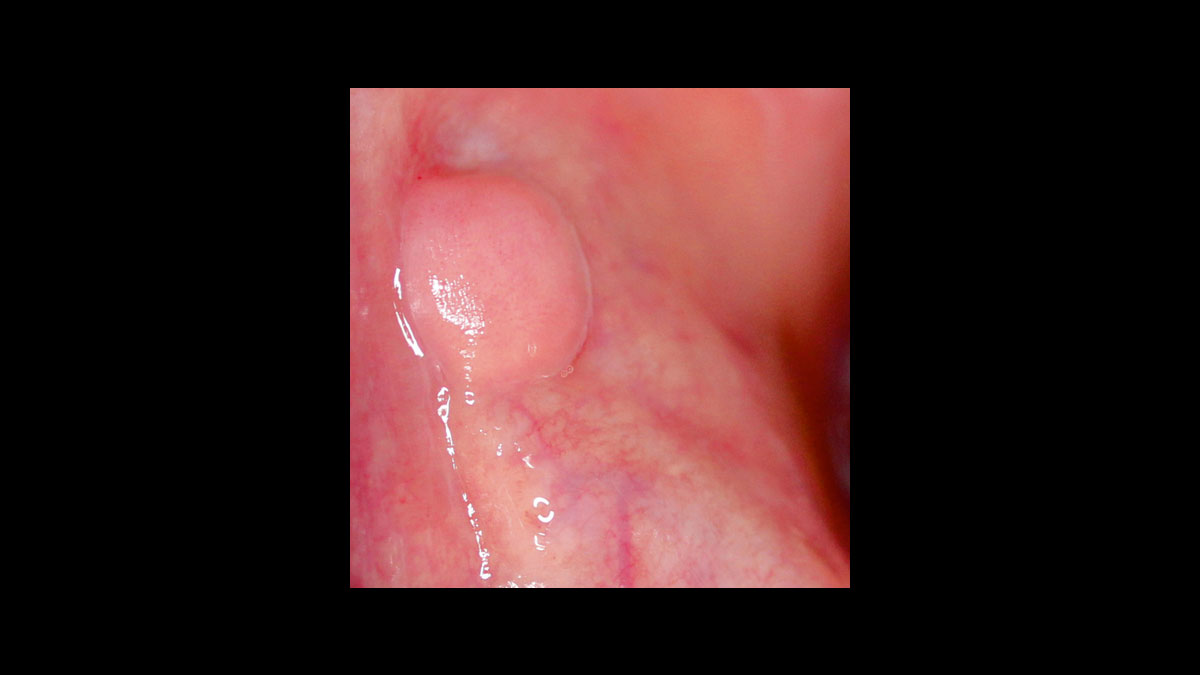

• Operculectomy

Operculectomy